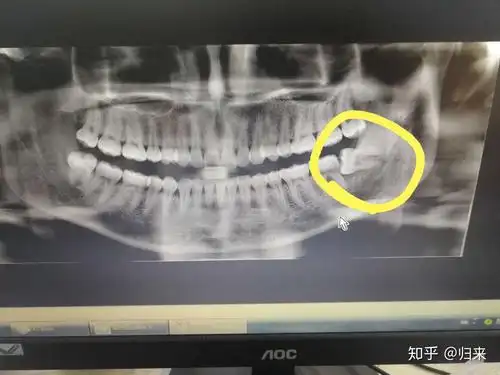

拔智齿有洗胃难受吗?